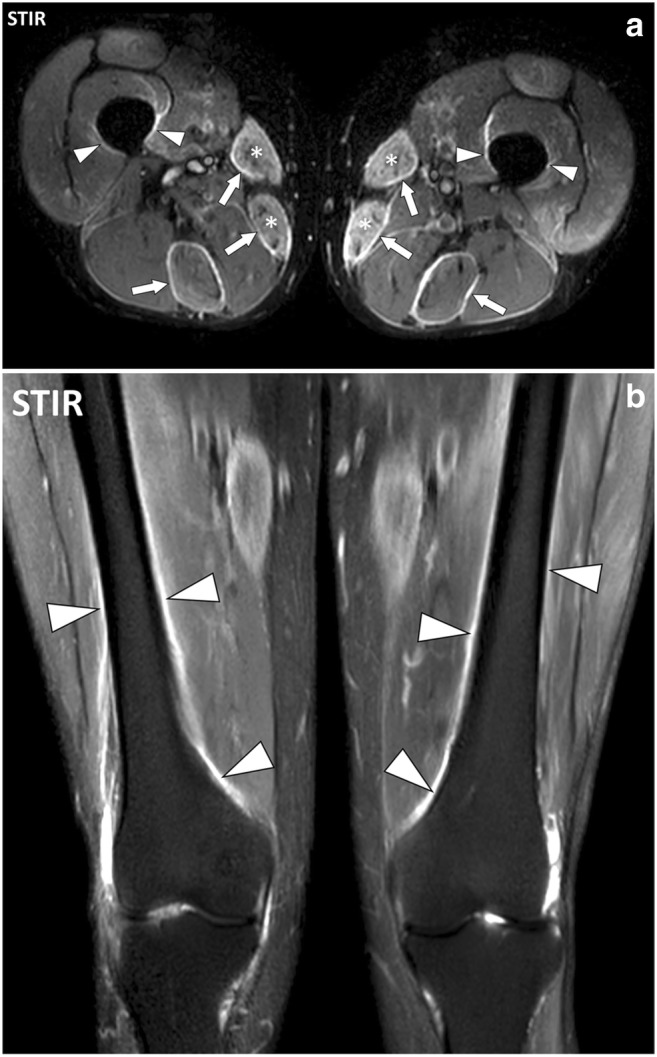

Fig. 18.

a Axial and (b) coronal STIR images of the thighs of a 51-year-old male with polymyositis. MRI demonstrates bilateral symmetrical involvement with myositis of the sartorius and gracilis muscles (asterisks), fasciitis of the deep fasciae adjacent to sartorius, gracilis and semitendinosus muscles (arrows) and periostitis mostly on the medial part of the diaphysis and metaphysis of the femurs (arrowheads)

Fig. 19.

Coronal STIR image of the thighs of a 43-year-old male with dermatomyositis (same as in Fig. 9). Involvement of the fascia superficialis of the medial part of the left thigh (asterisk) extends to the adjacent deep peripheral fascia (white arrows). The deep peripheral fascia of the right thigh (black arrow) and the subaponeurotic connective tissues of the left vastus lateralis muscle (arrowhead) are also involved